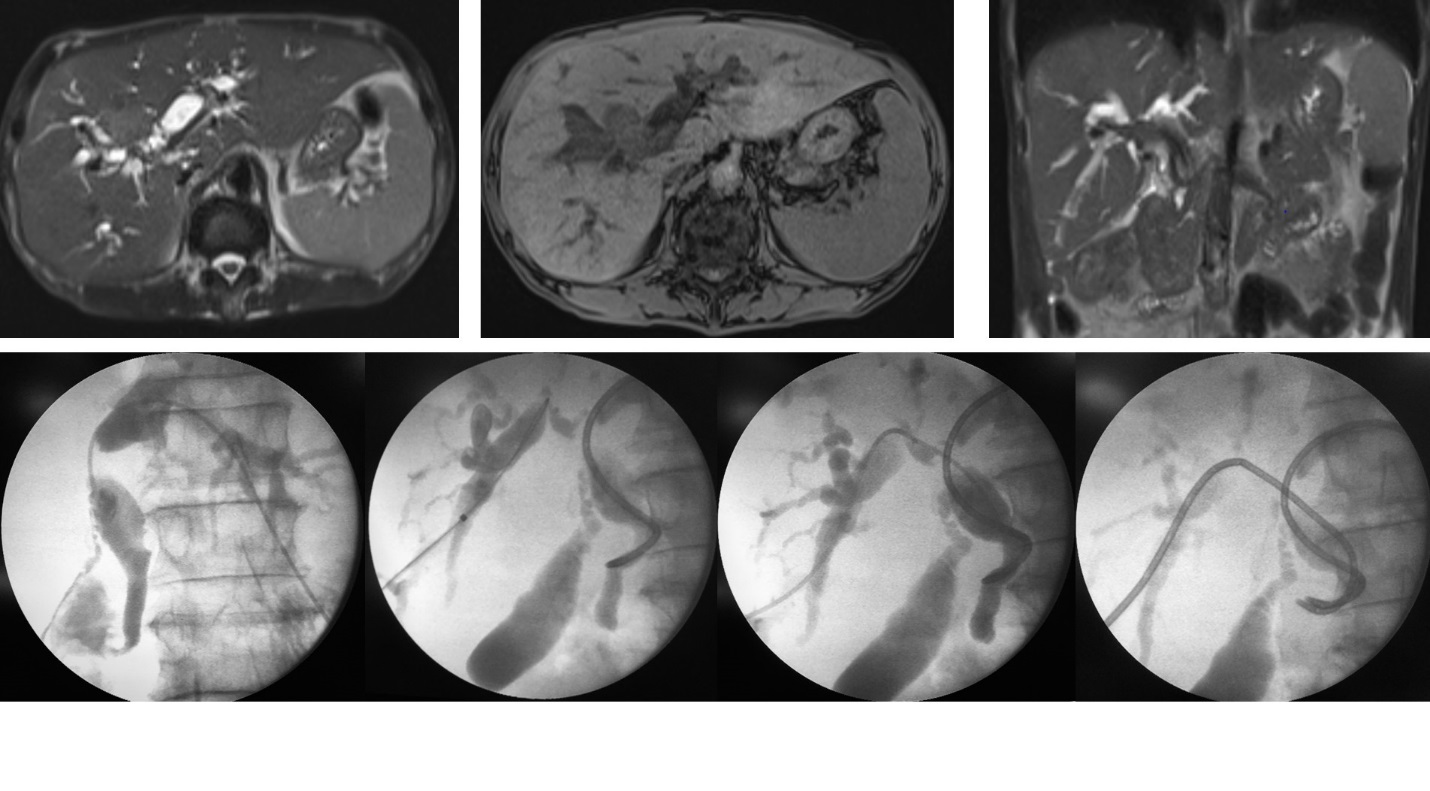

U đầu xa ống mật chủ. PTBD giảm áp và đặt stent ống mật chủ qua da tái thông đường mật.

U đường mật rốn gan (Klatskin) xâm lấn hai bên. PTBD giảm áp và đặt stent đường mật qua da hai bên hình chữ Y (Y configuration) tái thông đường mật.